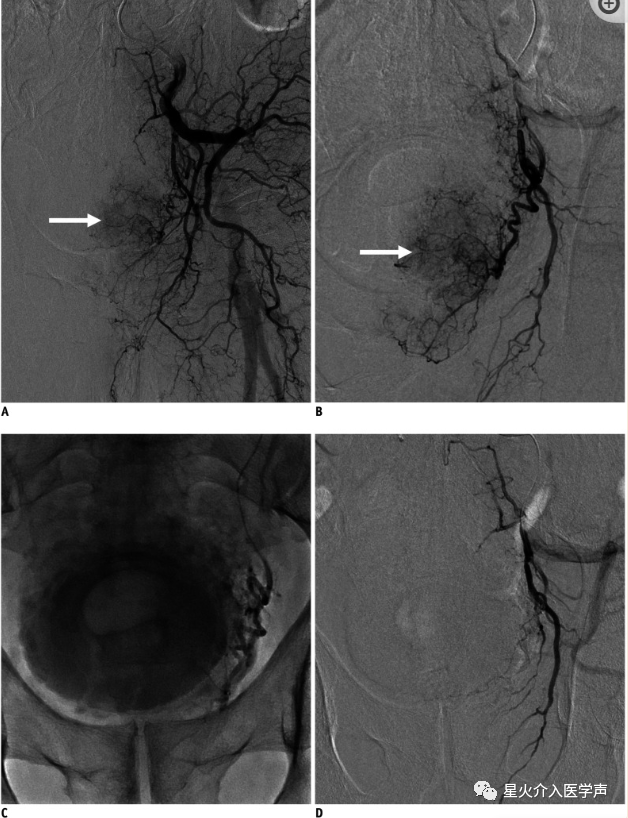

前列腺动脉栓塞术(PAE)是治疗良性前列腺增生继发下尿路症状的一种新兴疗法(图9) (37).在一系列病例中,TRA被用于PAE手术中TFA的潜在替代通路,所有病例都实现了双侧栓塞,技术上都取得了成功(38,39)。这两项研究的作者得出结论,通过TRA进行PAE在技术上是可行的,并提出了这种方法的优点,包括从可立即下床活动,减少住院时间等。最近的一项回顾性单中心研究比较了TRA和TFA进行PAE手术的结果,也表明经桡/尺入路是一种安全可行的方法,其安全性与TFA相当(20)。随着经桡介入学习曲线的进展,减少PAE手术时间、透视次数和辐射的可能性是有希望的。

桡动脉鞘怎么读经桡动脉通路外周介入治疗最新综述_https://www.jmylbn.com_新闻资讯_第11张

图9:TRA在前列腺动脉栓塞术中的临床应用。

A.左侧髂内动脉造影显示前列腺动脉染色,血管明显(箭头)。B选择性左前列腺动脉血管造影显示前列腺动脉染色(箭头)。C使用微导管选择前列腺动脉后,缓慢注射永久性栓塞剂(聚乙烯醇颗粒)直到血流接近停滞。D栓塞后左前列腺动脉血管造影显示前列腺动脉完全断流。